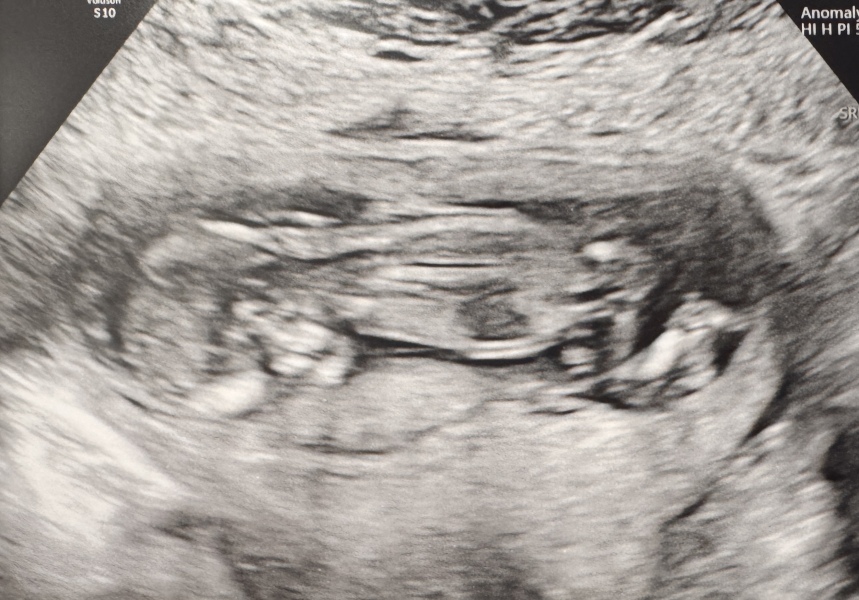

I’ll share a small update, especially for the older ladies like myself (41 in January). I’m 15+1 with a due date of 27th of May. Going by conception dates that’s a full week before we even had sex 😅 so dates definitely aren’t everything. This one is just a fast grower.

I had my 12 week scan early last week when they thought I’d be 13+4 and just scraped through measuring 13+6! And the baby was extremely lazy and obstinate! Refused to move from lying face down on the placenta with its little feet tucked up all comfy, didn’t matter how much I wriggled or walked or jumped about.

Got a good NT measurement of 1.8mm though, and I just had my blood test results through yesterday. A standard 1 in 5000 for Edward’s and Patau’s, and 1 in 350 for Down’s Syndrome which is around that of a 35 year old. So absolutely, definitely do not give up on your bodies just because of “statistics”. Praying for you all.

I know there’s still a ways to go with the anomaly scan and everything, but for now I’m feeling so very lucky. Just waiting to feel movement now!